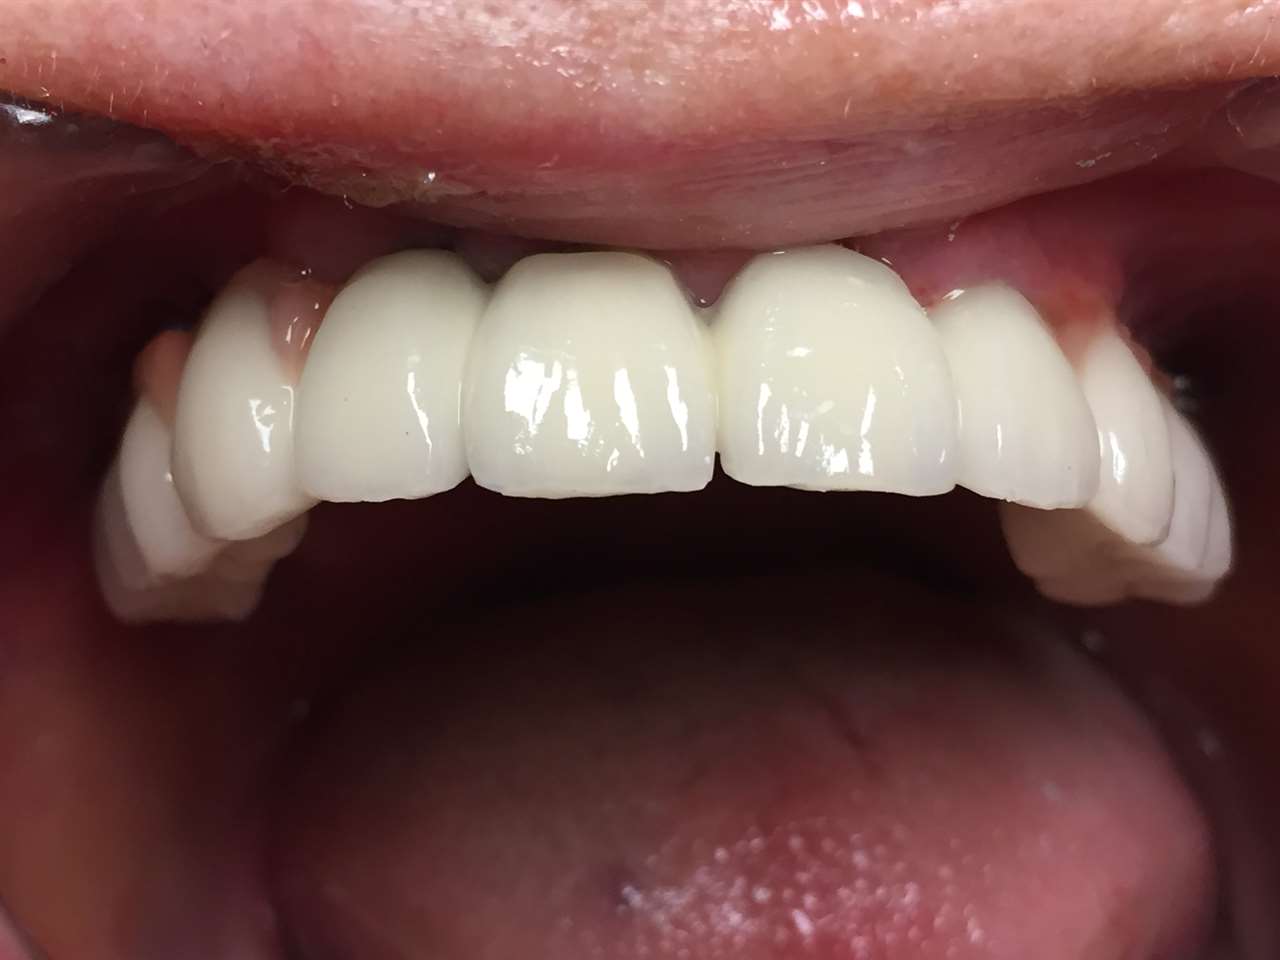

Teljes fogatlanság helyreállítása 2 nap alatt

Teljes fogatlanság helyreállítása 2 nap alatt azonnal terhelhető svájci IHDE implantátumokkal és PMMA műanyag hidakkal. Intraorális szkennerrel vettünk lenyomatot az implantáció után, és erre a digitális mintára készítette el a fogtechnika a hidak digitális tervezését, majd faragta ki műanyagból. Ezt a gyors munkát az azonnal terhelhető implantátumok és a digitális lenyomat, tervezés segítségével tudtuk megcsinálni mindössze 2 nap alatt. Dr. Kelemen Péter és a Symbion Fogtechnika munkája.